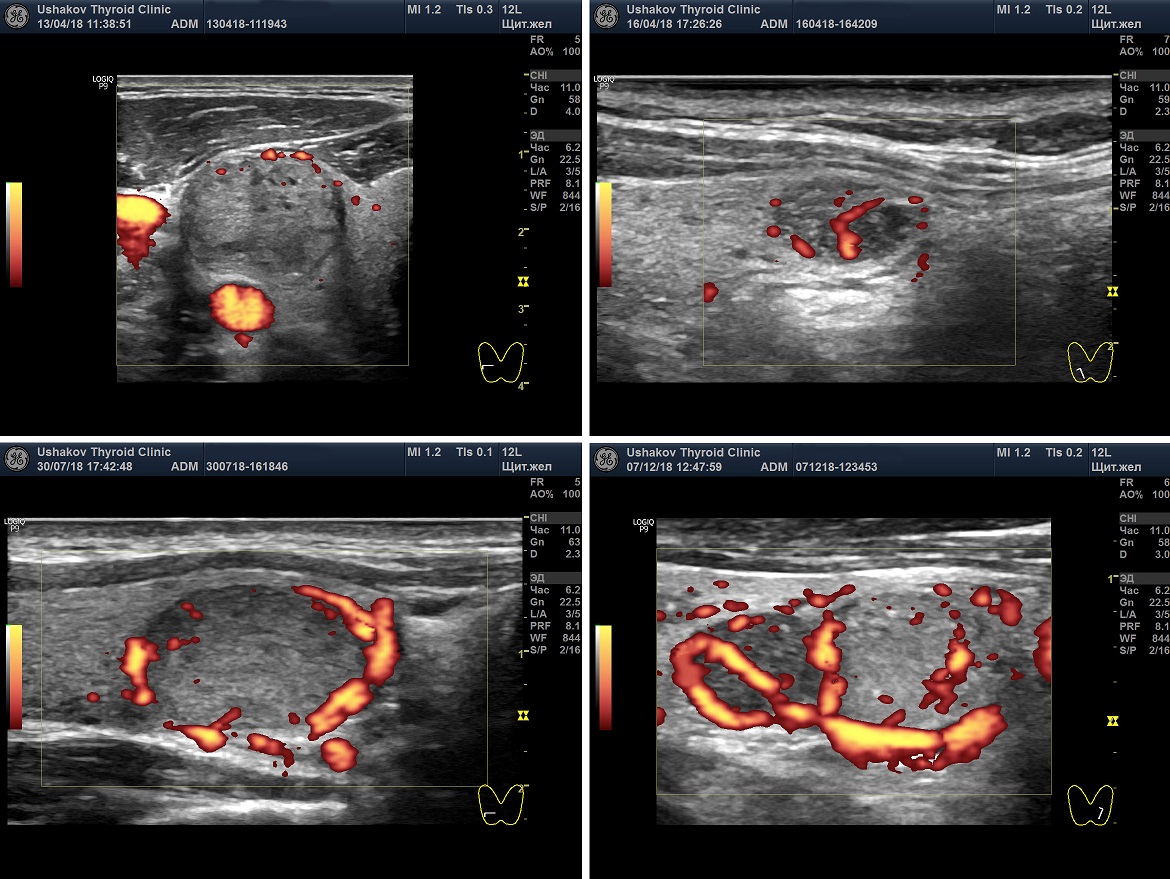

Интенсивность кровотока узлов щитовидной железы

При описании узлов в Протоколе УЗИ врач должен сообщить об интенсивности узлового кровотока и его особенностях расположения в узле. В режиме ЦДК или ЭДК.

Кровоток узла может быть ослабленным, малым, умеренным и значительным. Эта характеристика важна для оценки скорости и течения процессов в узлах. Определение величины интенсивности кровотока узлов поможет в прогнозе изменений узлов в соответствии с их стадиями.

Рисунок. 6. Интенсивность кровотока узлов щитовидной железы. Показаны несколько вариантов интенсивности кровотока: Малой интенсивности, Умеренной интенсивности, Значительной интенсивности.

Сосуды узла могут определяться по периметру и внутри узла. Информация о том, что кровоток узла «смешанный» (то есть внутри и вокруг узла) не имеет особой клинической ценности, так как может также часто встречаться как в доброкачественных, так и в злокачественных узлах.